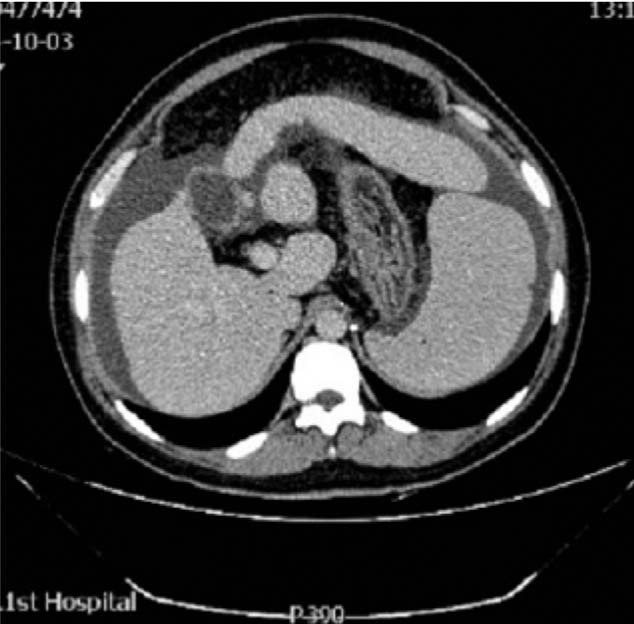

腹部CT检查提示肝硬化,脾肿大,腹水,门静脉高压,如图1。头部磁共振检查提示T1加权和T2加权高密度苍白球,代谢性脑病,如图2。骨髓穿刺提示巨幼红细胞性贫血,外周血涂片提示巨幼红细胞增多,血小板计数减少,给予谷胱甘肽治疗。

图1:腹部CT检查提示肝硬化,脾肿大,腹水,门静脉高压。